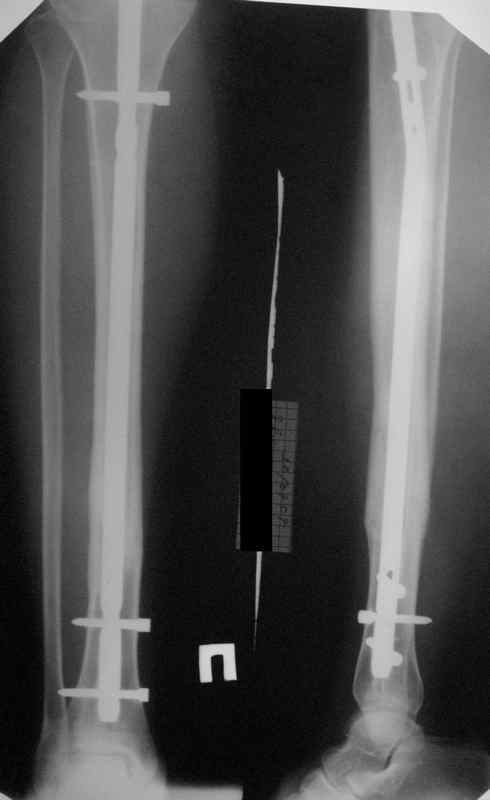

"Ходит с ограниченной нагрузкой на ногу. Направлен из травмпункта по поводу оставшегося смещения отломков. У нас разделилось мнение коллег по вопросу - есть ли необходимость в закрытом интрамедуллярном реостеосинтезе с исправлением оси или только ограничиться динамизацией гвоздя"

Техника введения штифта в дистальные переломы голени отличается от введения в c/3 диафиз. В дистальном отделе штифт надо ввести поглубже и блокировку внизу сделать на все возможные дистальные отверстия. В верхней части короткий штифт создает запас для будущей динамизации.

Одним из идеальных штифтом для лечения дистальных переломов голени является от Synthes Expert Nail, где имеется 4 возможные отверстия для дистальной блокировки, которые в различных направлениях создают дополнительную стабильность.

На снимке сохранен небольшой вальгус, но имеется нормальная аппозиция медиального кортикального слоя и поэтому трудно согласится что здесь имеется неправильно фиксированный перелом. Для идеального сопоставления таких косых переломов надо открывать фокус травмы, но тогда меняется философия фиксации.

Навряд ли рискованные манипуляции в фокусе травмы или ре-остеосинтез улучшит результат кроме рентгенологической картины.

Для предупреждения осложнении можно оставить как есть, потому что всего месяц с момента операции и не видно признаков несостоятельности остеосинтеза.

Отсутствие болей показания к нагрузке и после восстановления движения в суставе через пару-три недели можно сделать динамизацию. За редким исключением, обычно такие “неправильно фиксированные” переломы сростаются в срок.